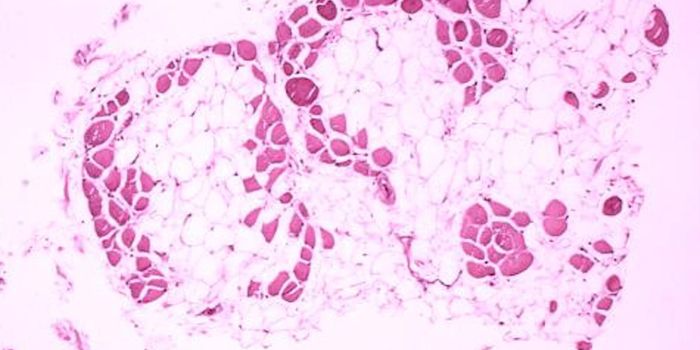

SEP 26, 2021Genetics & GenomicsMuscle diseases that have a genetic basis can cause muscles to waste away, and may lead to a premature death. There aren ...